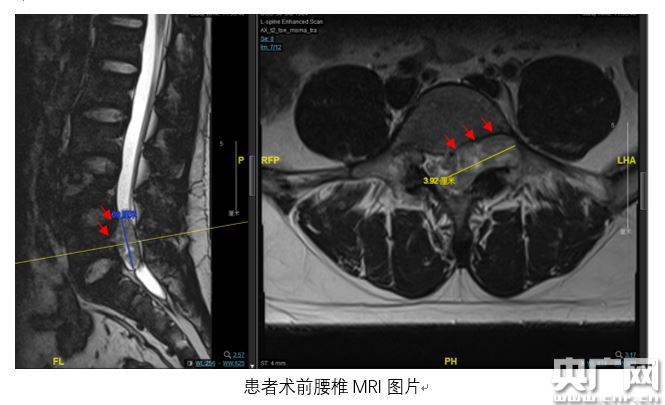

腰椎MRI檢查結(jié)果顯示,小陳腰骶部椎管內(nèi)有一個(gè)呈啞鈴型異常占位,占據(jù)了左側(cè)椎間孔且破壞到椎體骨質(zhì),憑借豐富臨床經(jīng)驗(yàn),趙杰主任診斷意見為椎管內(nèi)神經(jīng)鞘瘤,需盡快手術(shù)。